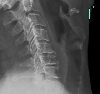

A conventional X-ray taken before surgery. Note the rather sinister "hook" on the front of the affected joints, where the bone is growing over the extruded discs (not visible in this X-ray). This is happening on the back side, which has to be removed. Getting rid of all that crunchy bone without harming the spinal cord is why neurosurgeons get paid a lot.

Contrast this X-ray with the next ones, where you can see the new artificial joints.